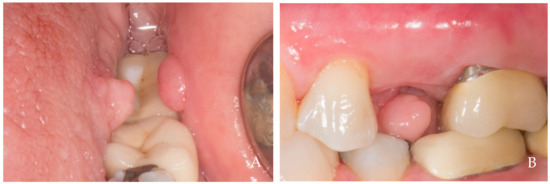

2. Clinical Examples of Oral Soft Tissue Growth